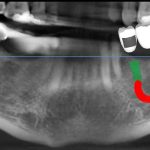

تصویربرداری سه بعدی( CBCT):

اسکن سه بعدی فک و دندان ها انجام میشود تا ساختارهای دقیق استخوان و موقعیت عصب ها مشخص شود